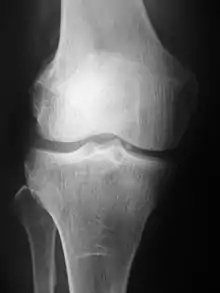

Radiographs (originally called roentgenographs, named after the discoverer of X-rays, Wilhelm Conrad Röntgen) are produced by transmitting X-rays through a patient. The X-rays are projected through the body onto a detector; an image is formed based on which rays pass through (and are detected) versus those that are absorbed or scattered in the patient (and thus are not detected). Röntgen discovered X-rays on November 8, 1895, and received the first Nobel Prize in Physics for his discovery in 1901.

In film-screen radiography, an X-ray tube generates a beam of X-rays, which is aimed at the patient. The X-rays that pass through the patient are filtered through a device called a grid or X-ray filter, to reduce scatter, and strike an undeveloped film, which is held tightly to a screen of light-emitting phosphors in a light-tight cassette. The film is then developed chemically and an image appears on the film. Film-screen radiography is being replaced by phosphor plate radiography but more recently by digital radiography (DR) and the EOS imaging.[5] In the two latest systems, the X-rays strike sensors that converts the signals generated into digital information, which is transmitted and converted into an image displayed on a computer screen. In digital radiography the sensors shape a plate, but in the EOS system, which is a slot-scanning system, a linear sensor vertically scans the patient.

Plain radiography was the only imaging modality available during the first 50 years of radiology. Due to its availability, speed, and lower costs compared to other modalities, radiography is often the first-line test of choice in radiologic diagnosis. Also despite the large amount of data in CT scans, MR scans and other digital-based imaging, there are many disease entities in which the classic diagnosis is obtained by plain radiographs. Examples include various types of arthritis and pneumonia, bone tumors (especially benign bone tumors), fractures, congenital skeletal anomalies, and certain kidney stones.